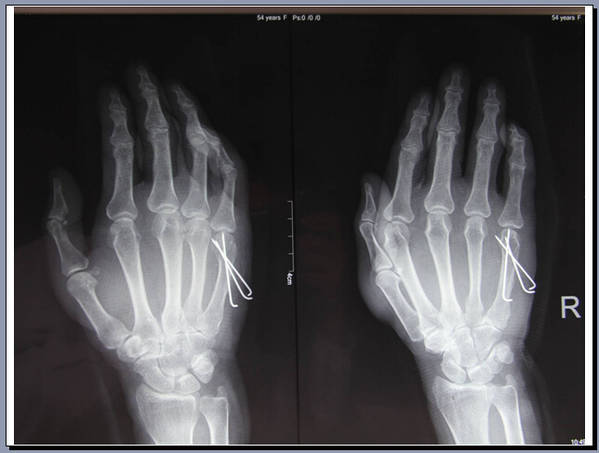

手外科会议带去一个讨论题目